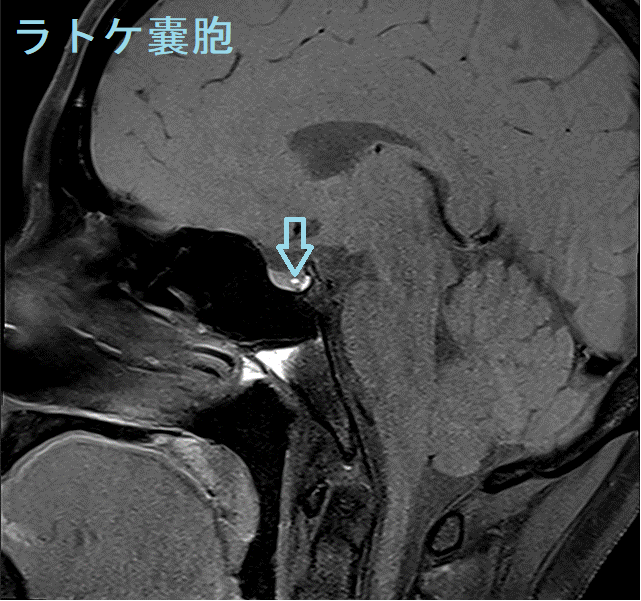

ラトケ嚢胞(ラトケのう胞)とは胎児期の袋が消えずに残ったものです。

MRI検査では

- T1強調;50% 高信号(蛋白成分が多い)、50% 低信号

- T2強調;70% 高信号、30% 等-低信号

- T1+ Gd造影剤;造影効果なし、周囲辺縁のみ造影される